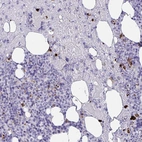

Immunohistochemical staining of human bone marrow shows strong positivity in a subset of hematopoietic cells.